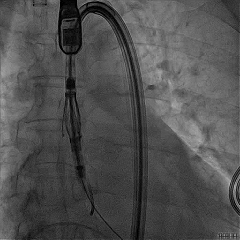

TEER手术过程

建立右侧股静脉入路,在食道超声引导下进行房间隔穿刺,获得穿刺高度4.1cm,交换Super Stiff超硬导丝至左上肺静脉,使用血管鞘扩张股静脉后,沿超硬导丝送入可操控导引导管(SGC)至左房,将第一枚二尖瓣夹输送系统(CDS-XTR)送入左心房。送入夹子过程中为避免碰到左房组织完成Straddle“骑跨”,顺利完成Straddle并将夹子打弯至二尖瓣环水平。接下来为避免发生缠绕在1区进行轨迹测试,使夹子的运动轨迹指向心尖。在心房侧打开夹臂,调整夹臂方向指向12点-6点方位,与二尖瓣对合缘垂直。完成调整后将夹子移动至3区位置,将二尖瓣夹关紧后缓慢送入左心室。在左室打开夹子重新确认Orientation。准确成功捕捞3区前叶脱垂及反流区域,确认瓣叶瓣尖稳定插入夹臂后,Gripper Down,观察到明显Bouncing后,关紧夹臂予以夹合,夹子内侧反流消失,夹子外侧还有残余脱垂及中量反流。考虑瓣叶长度11mm以上,瓣口面积足够,决定在外侧Side by Side再植入一枚XTR,植入两枚XTR后活动稳固,反流降至Trace。术后肺静脉逆流消失,二尖瓣平均跨瓣压差2mmHg。

房间隔穿刺高度4.1cm

SGC穿房间隔进入左房

第一枚XTR进入左房

在1区进行轨迹测试和Orientation调整

将调整好的夹子移动至3区下左室

在左室打开夹子确认Orientation